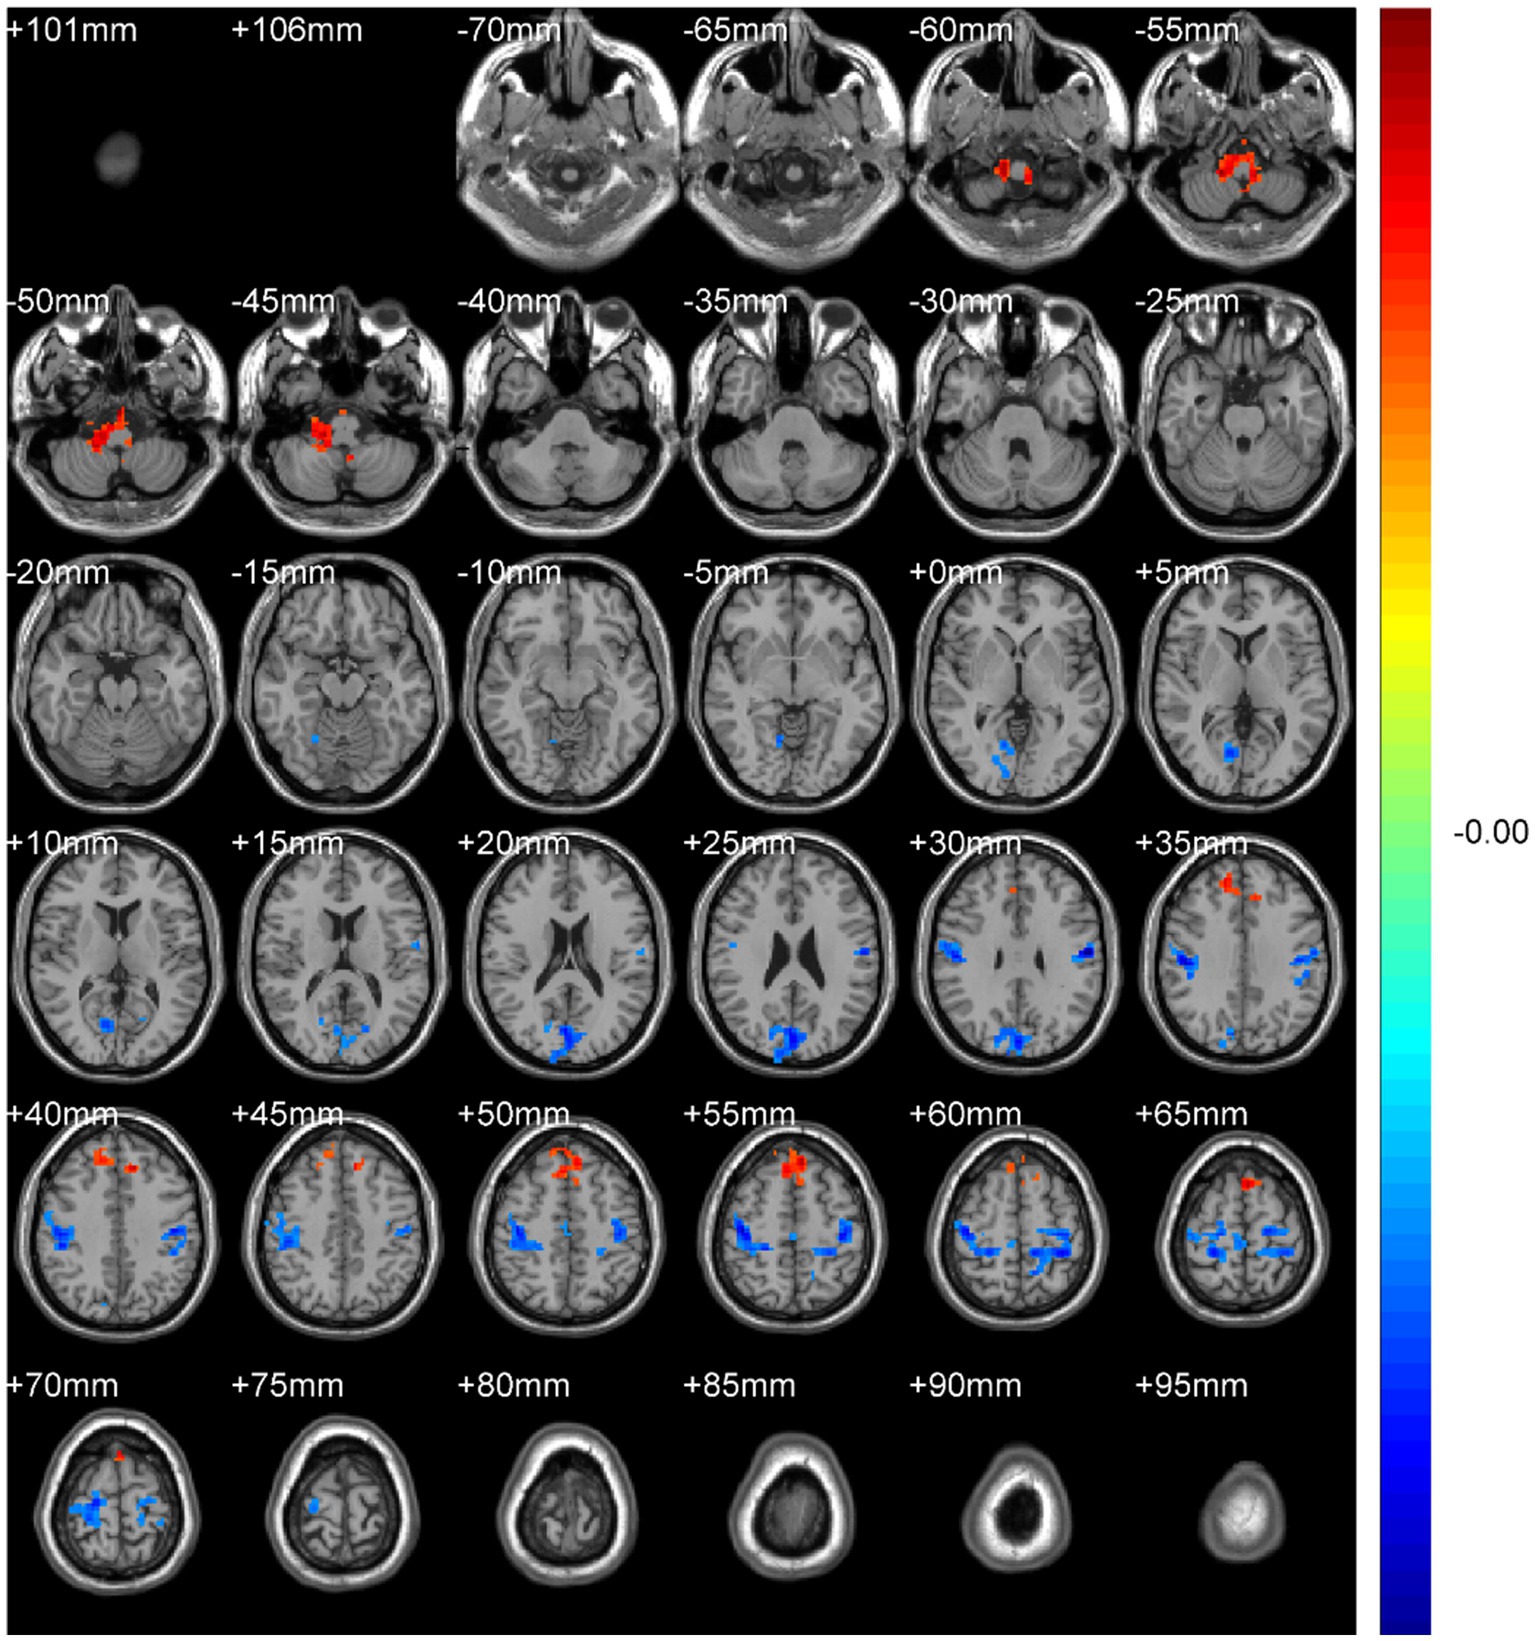

ABSTRACT Background: Spinal diseases related pain represents a critical clinical issue that demands urgent resolution. Current treatment and assessment strategies predominantly focus on peripheral mechanisms. The application of functional magnetic resonance imaging (fMRI) offers a promising approach to identifying potential central targets for intervention. Methods: We retrospectively included 31 patients with spinal diseases related pain and 32 controls with non-spinal, orthopedic complaints (no chronic neurological or psychiatric disorders). All participants underwent resting-state brain fMRI (eyes closed, awake). We quantified amplitude of low-frequency fluctuations (ALFF) with mean normalization (mALFF) and z-transformation (zALFF), regional homogeneity (ReHo; 27-voxel neighborhood), seed-based functional connectivity (FC; pre/postcentral seeds), and degree centrality (DC; binary and weighted). Between group tests used voxel-wise two-sample t_tests with Gaussian Random Field (GRF) correction. Results: Patient group was associated with increased m/zALFF in right cerebellar lobule IX and right Superior Frontal Gyrus, medial part , and lower activity in bilateral postcentral gyri and the Cuneus. , decreased m/zALFF in bilateral postcentral gyri. ReHo analysis confirmed reduced local synchrony in postcentral regions , spatially overlapping with ALFF findings. FC analyses revealed enhanced cerebellar-thalamic connectivity (Crus1/2, thalamus) but reduced connectivity in sensorimotor and higher-order cortical networks. DC showed hyperconnectivity in left cerebellar Crus I with reduced Superior Frontal Orbital (Frontal_Sup_Orb). All findings survived GRF correction at the pre_specified thresholds. Conclusions: Resting-state brain fMRI indicates a cerebello-thalamo-cortical alteration pattern in spinal diseases related pain featuring cerebellar involvement, prefrontal subspecialization, and multilevel sensorimotor disruption. These cross-sectional associations may inform hypothesis-generation for future neuromodulation studies and provide candidate biomarkers for monitoring, pending prospective validation.